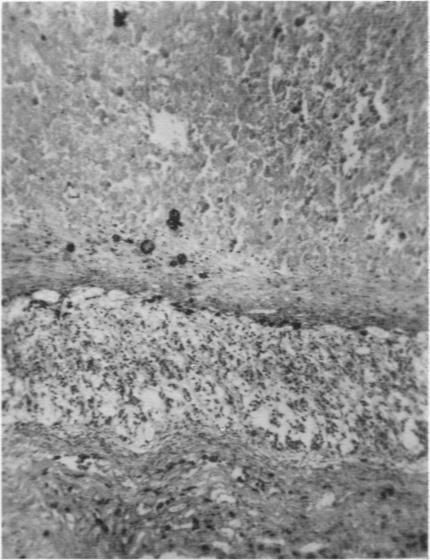

Addison's disease in infancy.

Arch Dis Child. 1956 Aug;31(158):265-9. doi: 10.1136/adc.31.158.265.